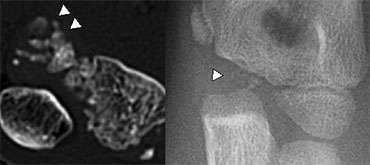

Fragmented appearance of the Trochlea in 2 different children. Fragmented appearance of the Trochlea in 2 different children.

The Trochlea has two or more ossification centres which can give the trochlea a fragmented appearance.

Trochlea ossification-fragments simulate loose bodies in the joint Trochlea ossification-fragments simulate loose bodies in the joint

On a lateral view the trochlea ossifications may project into the joint.

They should not be mistaken for loose intra-articular bodies (arrow).